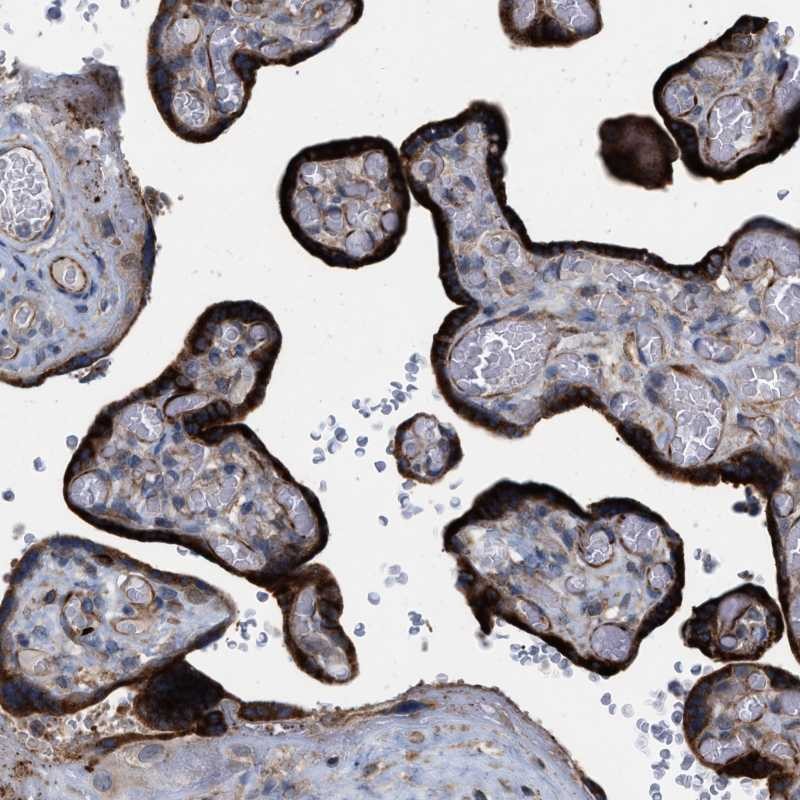

Immunohistochemical staining of human placenta shows strong cytoplasmic positivity in trophoblastic cells.